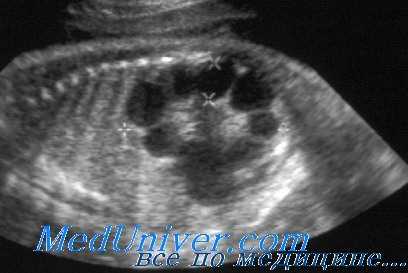

При УЗИ почки резко увеличены, но форма их сохранена. Паренхима имеет повышенную эхогенность, крупнозернистая, с наличием мелких эхонегативных зон («соль с перцем»). На более поздней стадии помимо веретенообразных могут появиться кисты сферической формы. УЗИ печени выявляет повышенную эхогенность, а позднее — хорошо различимые кисты желчных протоков.

УЗИ при поликистозе почек